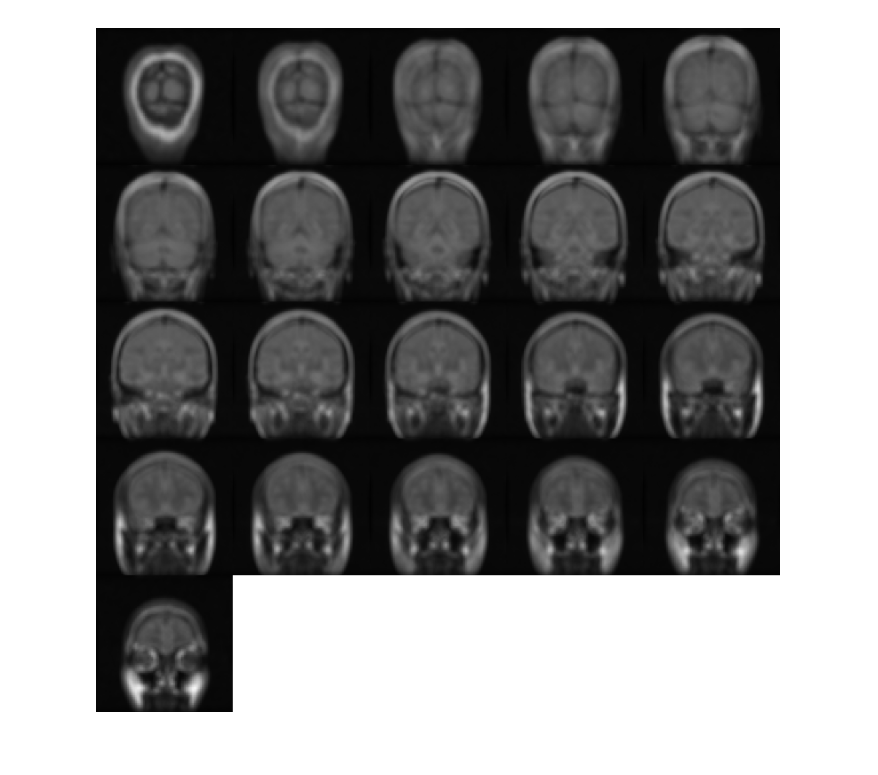

Загрузите 3-D полутоновый объем МРТ. Отображение плоскостей объема.

load mristack;

montage(mristack,'BackgroundColor','w')

Figure contains an axes. The axes contains an object of type image.